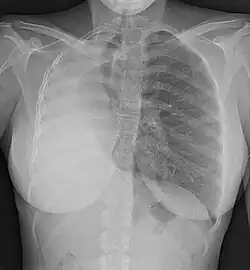

Chest X-ray showing pulmonary hypoplasia

Pulmonary hypoplasia